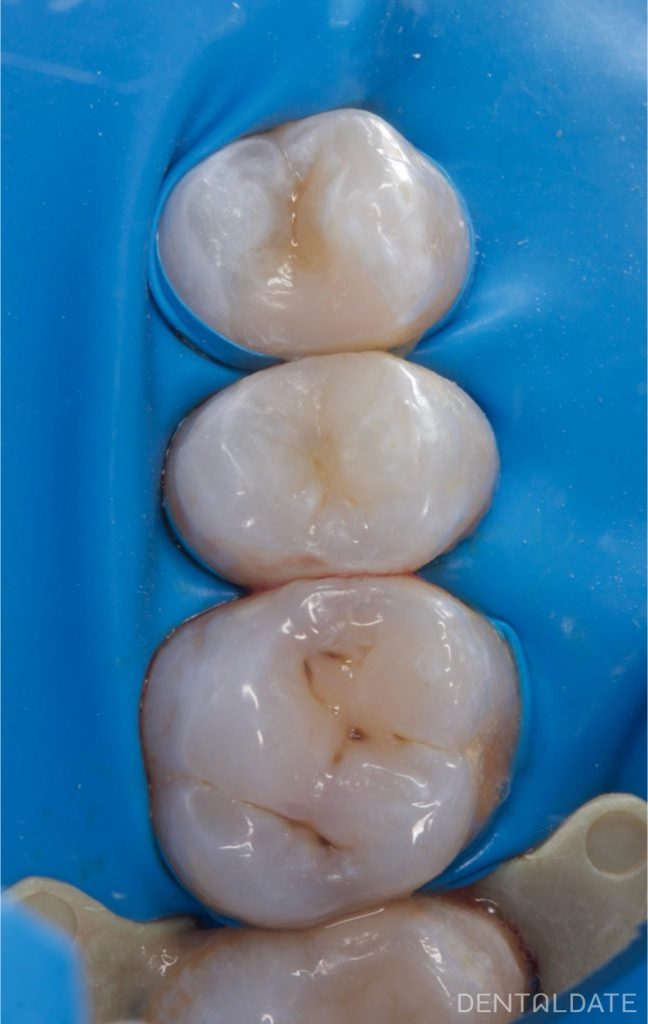

Caries on the contact surfaces is difficult to detect without a microscope.

During treatment, decay was also discovered on a neighbouring tooth.